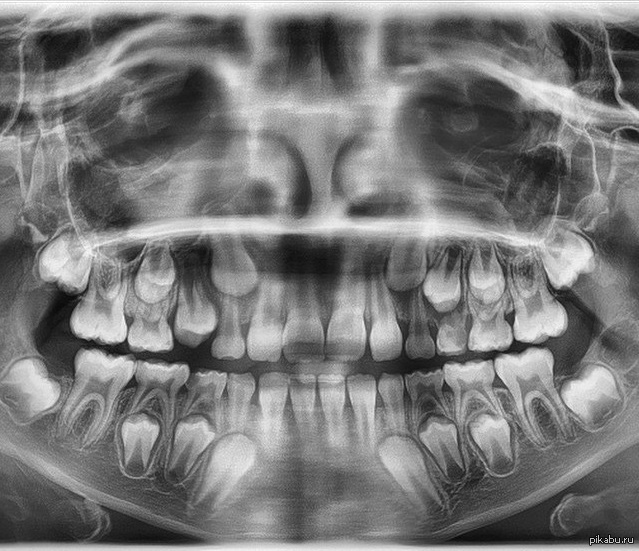

Дентальные снимки и диагностика кариеса